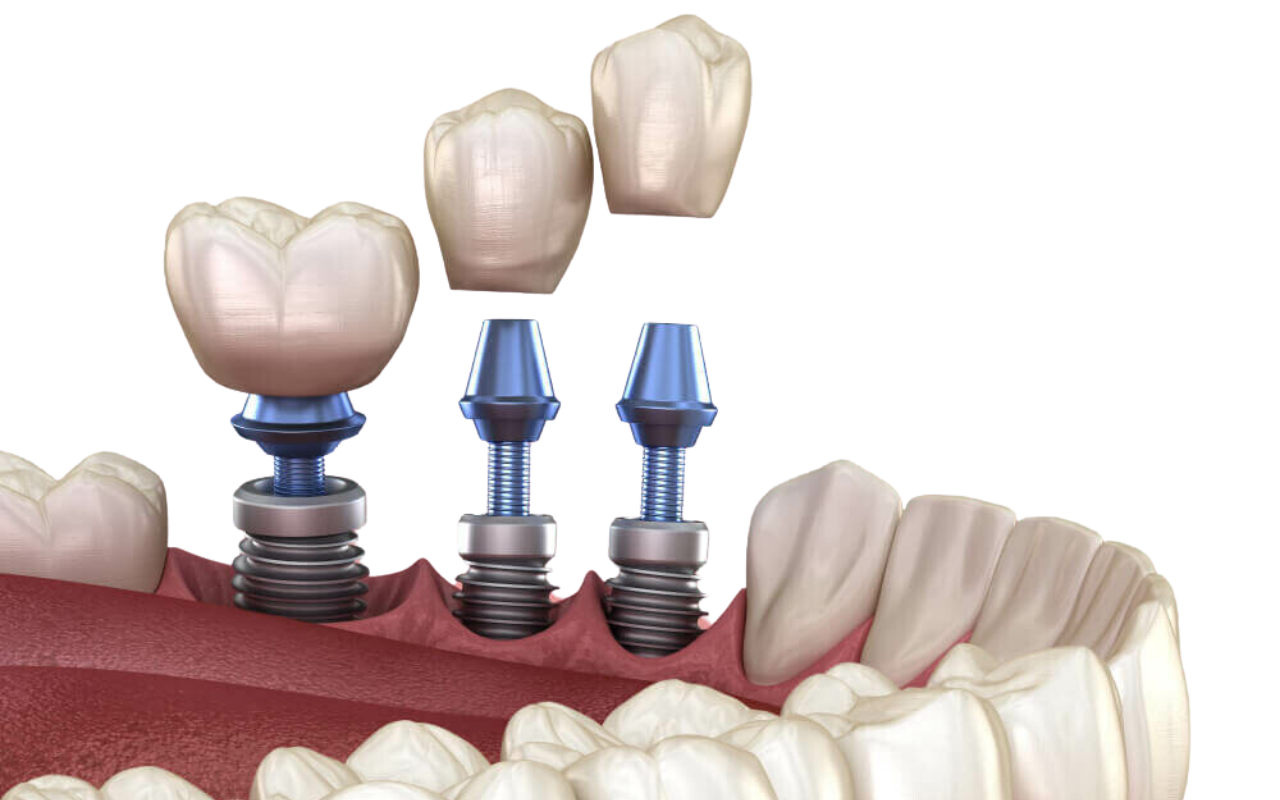

Advanced Technology for Superior Care

GDental is equipped with state-of-the-art technology, including digital imaging and 3D scanning, to enhance the accuracy and comfort of dental implant procedures. This cutting-edge technology allows Dr. Pasisnitchenko to provide superior outcomes, ensuring long-lasting, natural-looking results.